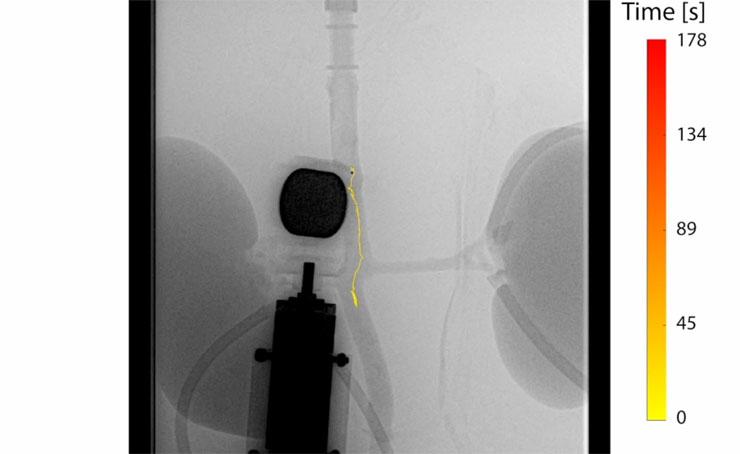

Voor het experiment gebruikten de onderzoekers een draaiende magneet bestuurd door een robotarm om de millirobots draadloos door het bloedvat te sturen. Met een röntgenapparaat lokaliseerden ze de millirobots terwijl deze door de aorta zwommen. De onderzoekers gebruikten een maximale bloedstroom in de aorta van 120 ml per minuut. Maar met een sterkere magneet kunnen de millirobots door een sterkere stroming zwemmen. De millirobots zwommen stabiele rechte stukken met de stroom mee en tegen de stroom in. Dat lukte met één, maar ook met meerdere robots tegelijk.